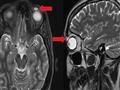

وأجرت المرأة فحوصات على عينها، بعد أن عانت من انتفاخ وتدلي في الجانب الأيسر من الجفن منذ ستة أشهر، وأظهرت الأشعة أن المشكلة الصحية ناتجة عن وجود عدسة بحجم 8 ميليمترات، وهو ما جعل الطبيب يلجأ إلى الجراحة لإزالة العدسة التي ظلت في مكانها قرابة ثلاثة عقود.